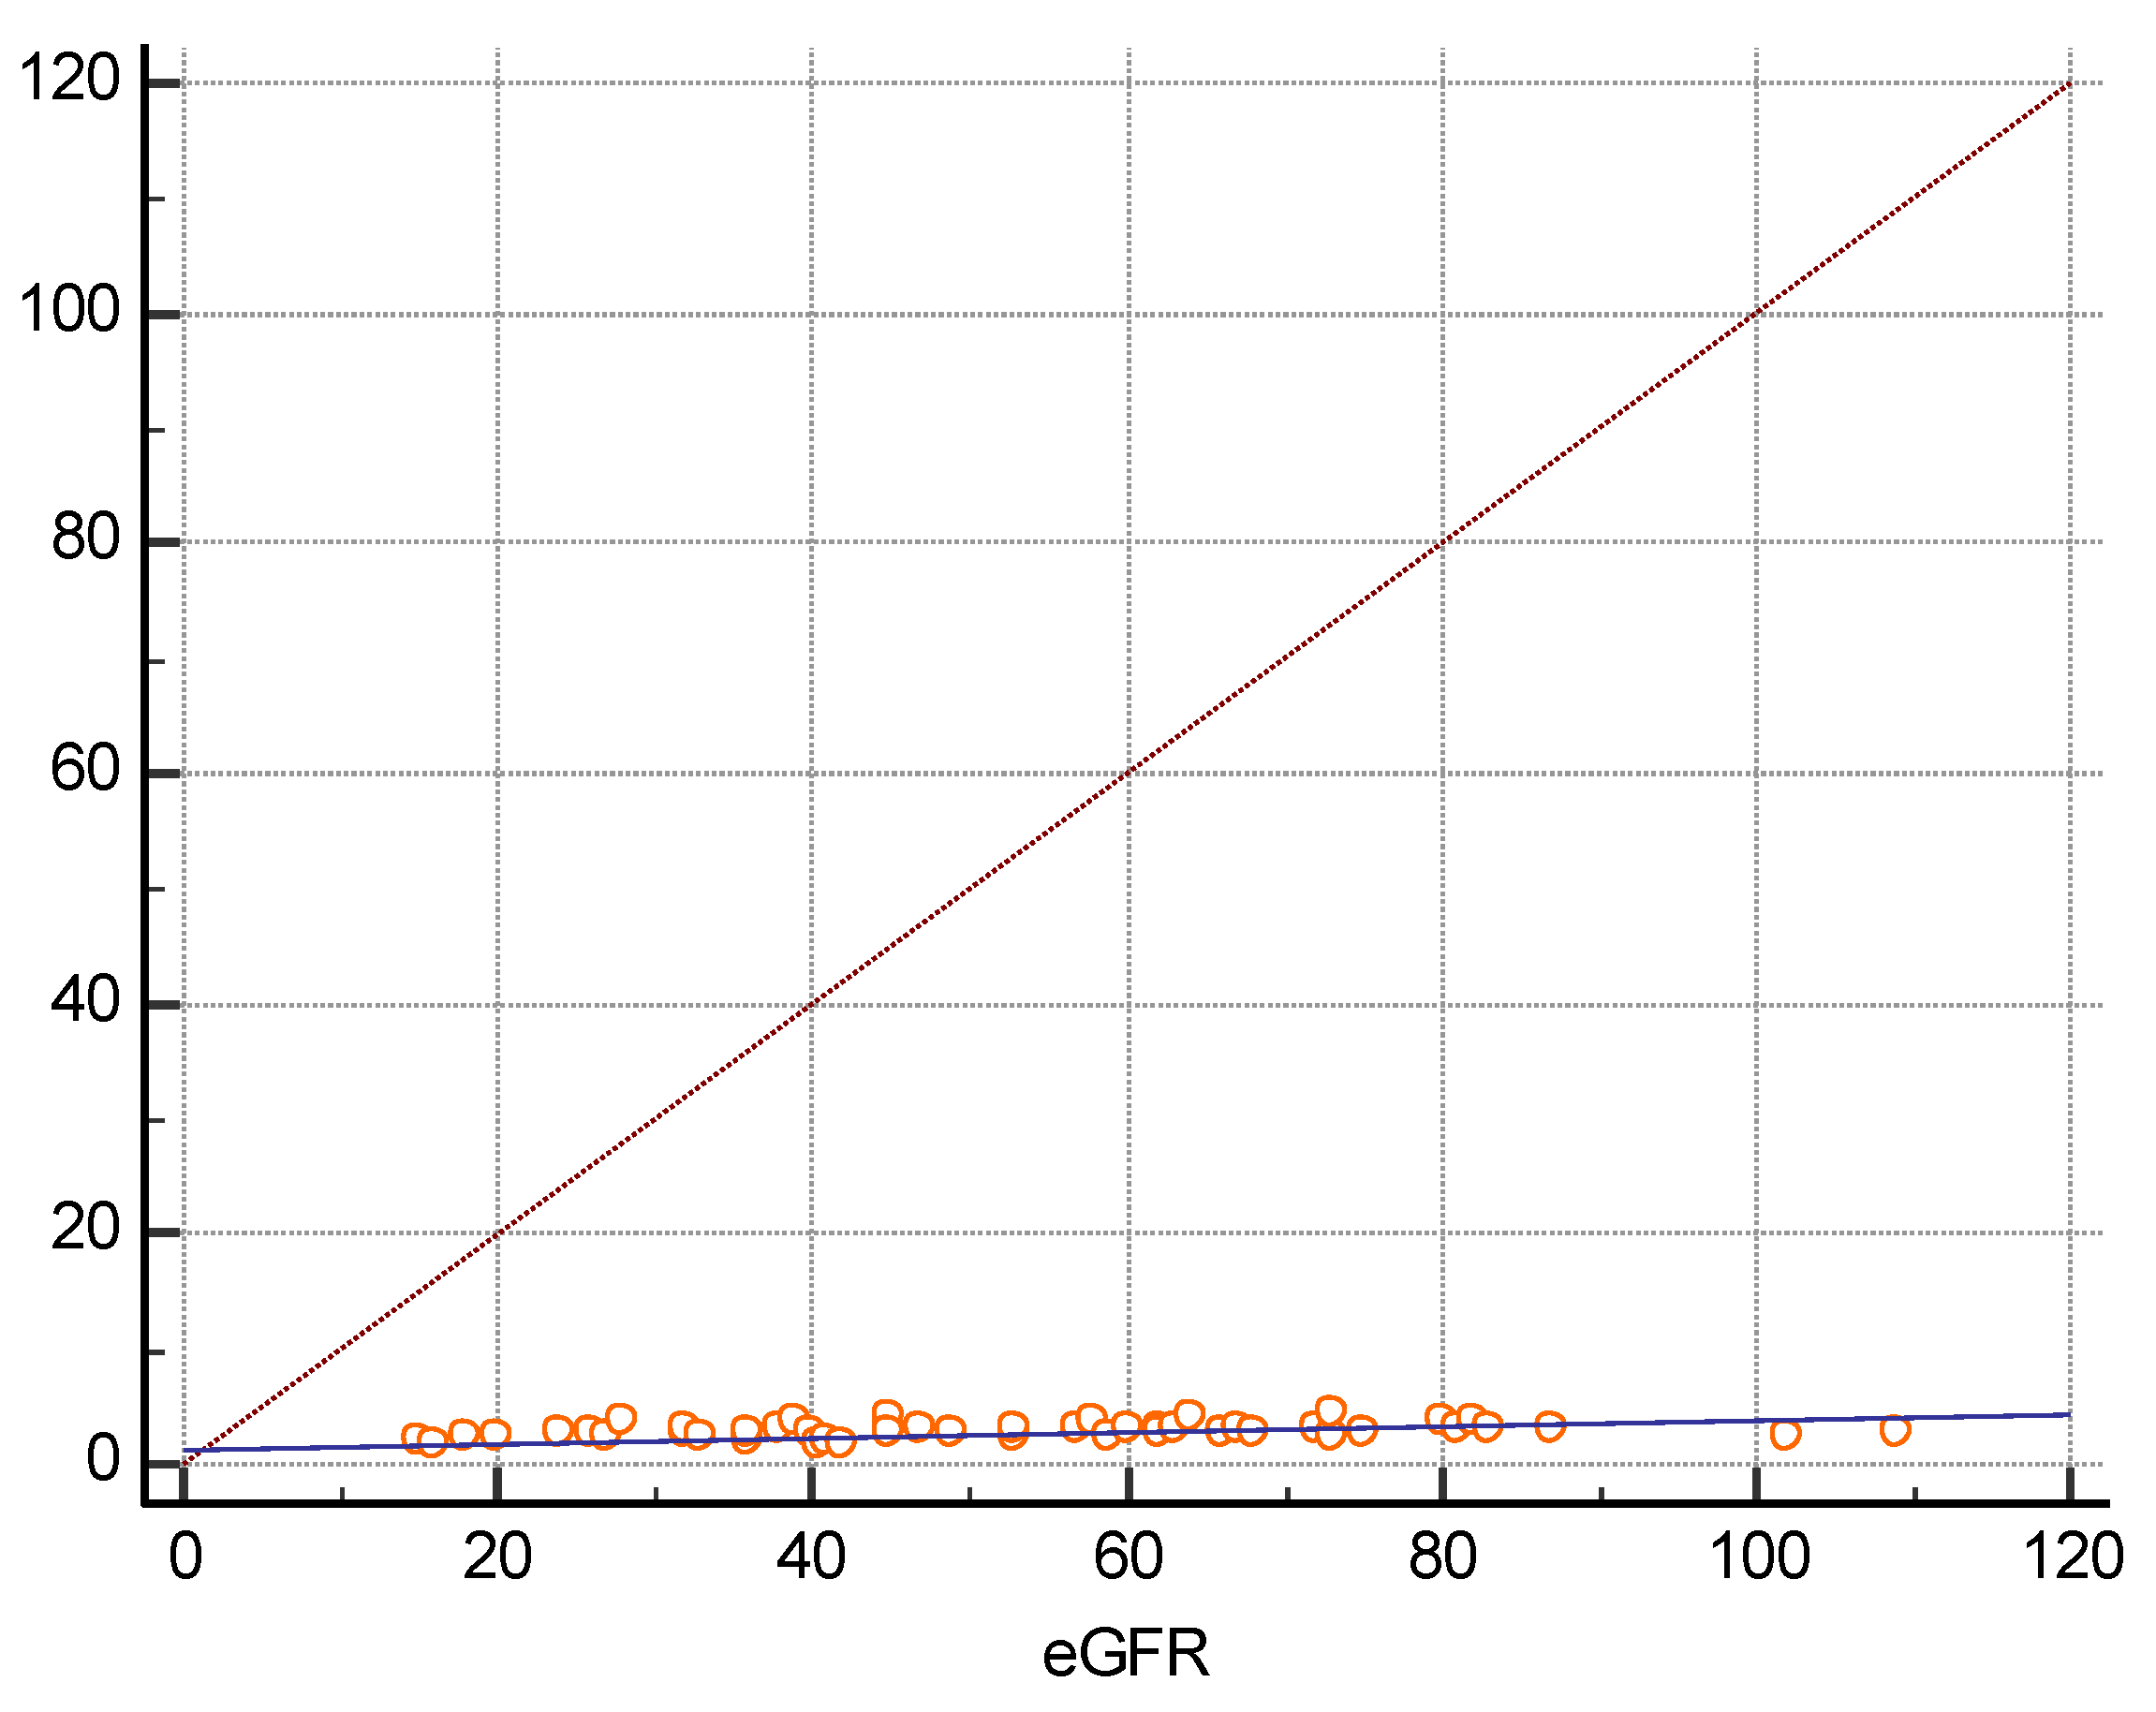

3. Results

| eGFR (mL/min/1.73m2) | 52 ± 22.6 | 0.5699 | p < 0.0001 |